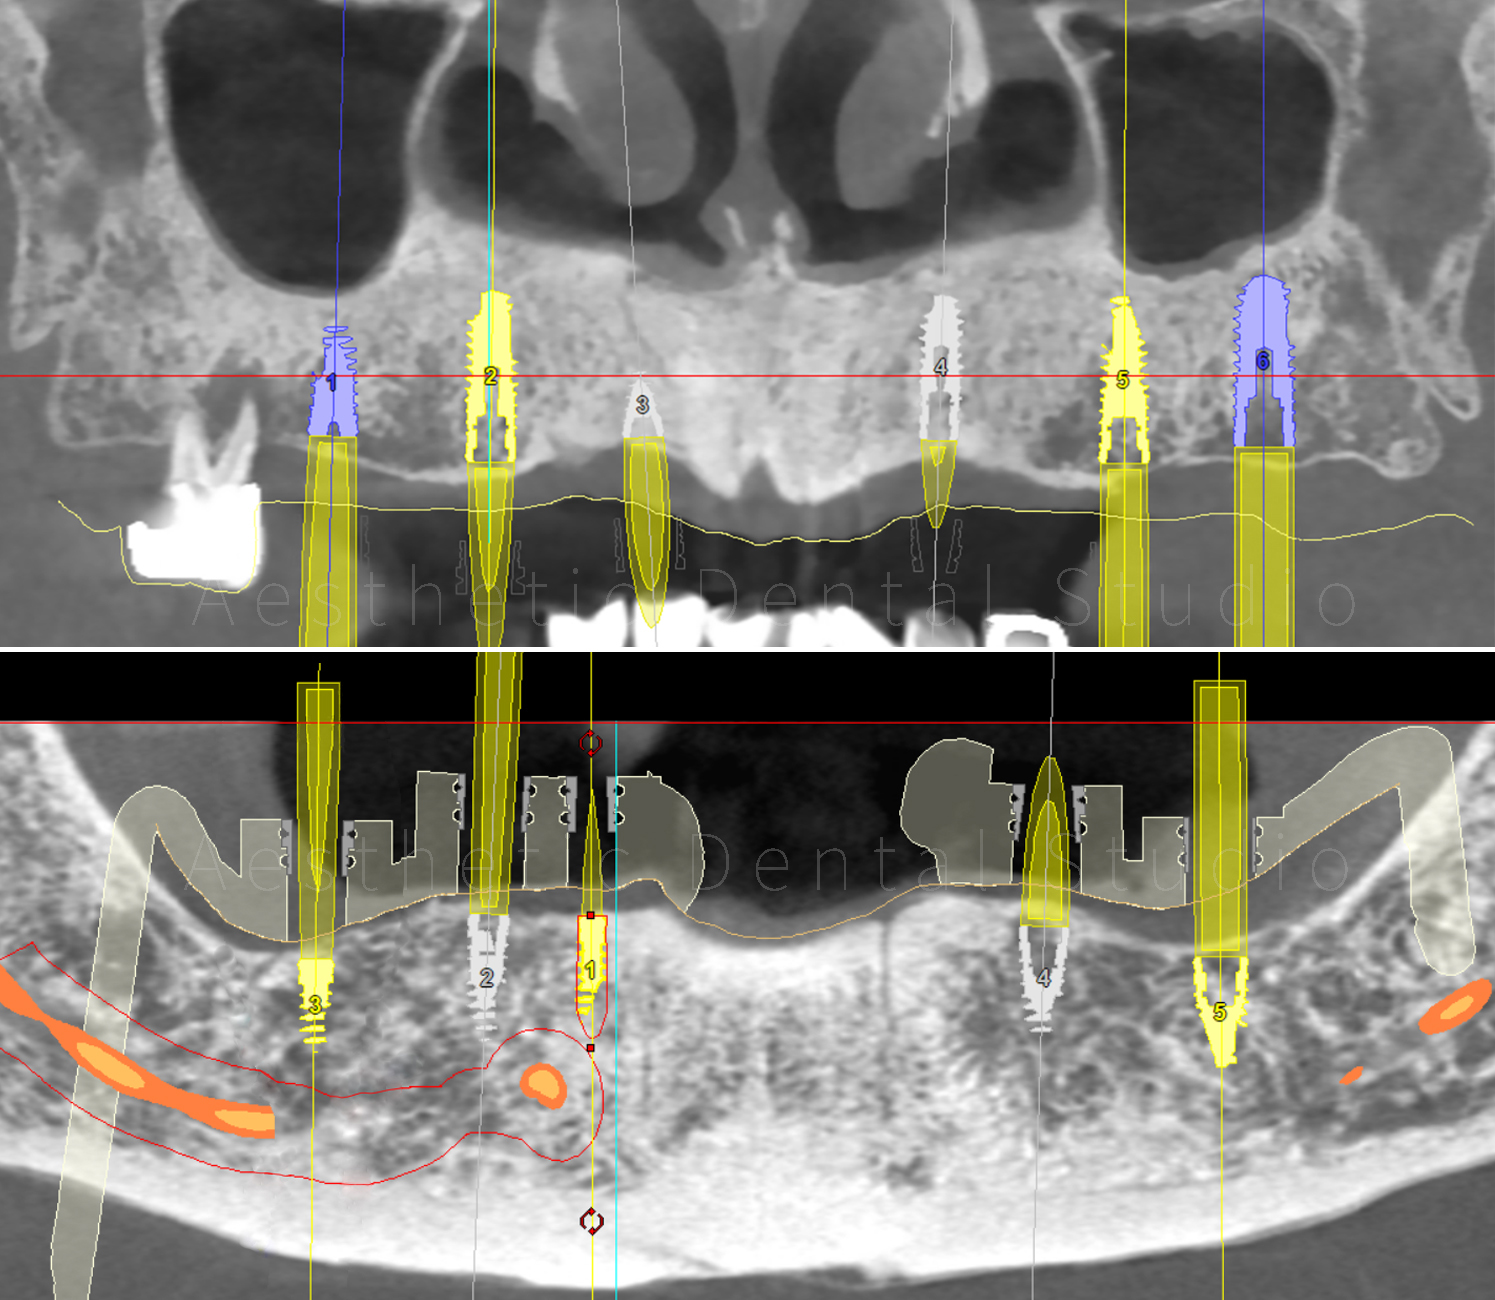

Με εξειδικευμένο οδοντιατρικό λογισμικό έγινε ψηφιακός σχεδιασμός και εικονική τοποθέτηση των εμφυτευμάτων, ώστε να εξασφαλιστεί απόλυτη ακρίβεια και ασφάλεια.

Ο σχεδιασμός στάλθηκε σε εξειδικευμένο κέντρο στη Γερμανία, όπου δημιουργήθηκε τρισδιάστατος χειρουργικός οδηγός, προσαρμοσμένος στο στόμα της ασθενούς.

Αυτός ο οδηγός χρησιμοποιήθηκε στο χειρουργείο για την τοποθέτηση συνολικά 11 εμφυτευμάτων με ακρίβεια χιλιοστού:

• 6 στην άνω γνάθο

• 3 στην κάτω δεξιά περιοχή

• 2 στην κάτω αριστερή περιοχή

Με αυτό τον τρόπο δημιουργήθηκε ένα σταθερό υπόστρωμα για την προσθετική αποκατάσταση ολόκληρου του στόματος.